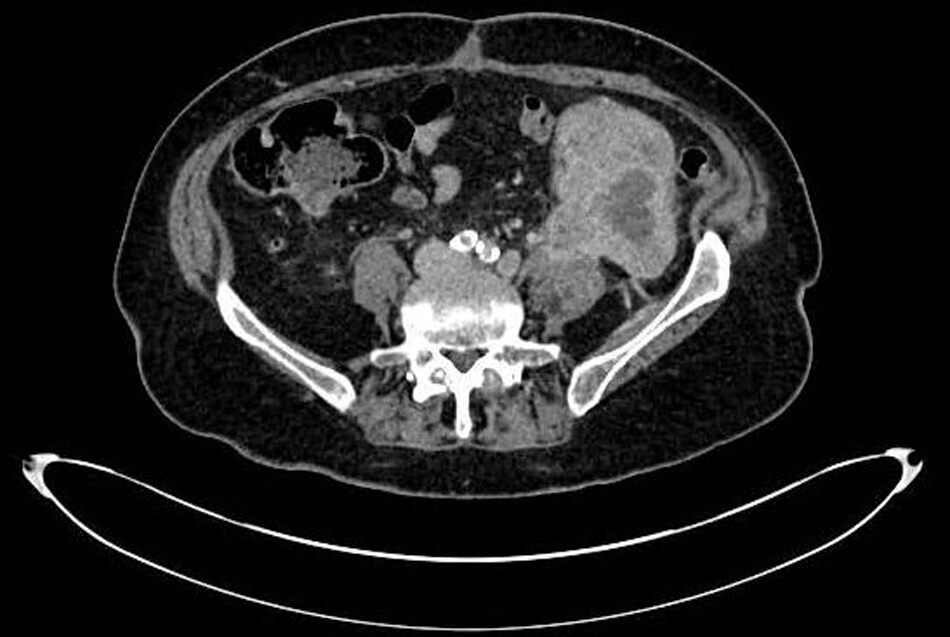

Figure 1: Axial CT section demonstrating upper tract CCUC recurrence in left retroperitoneum.

She re-attended via the emergency department two months postoperatively with left flank pain and significantly raised inflammatory markers. A left-sided 8.3 x 6.5cm retroperitoneal mass with new para-aortic lymphadenopathy was identified on CT abdomen / pelvis and was diagnosed as recurrent disease (Figures 1 and 2). This was engulfing the descending colon and extended inferiorly to psoas. She was treated with intravenous antibiotics and reviewed by oncology but deemed too unfit for systemic oncological treatment in the context of her acute illness. She died three months after her operation.